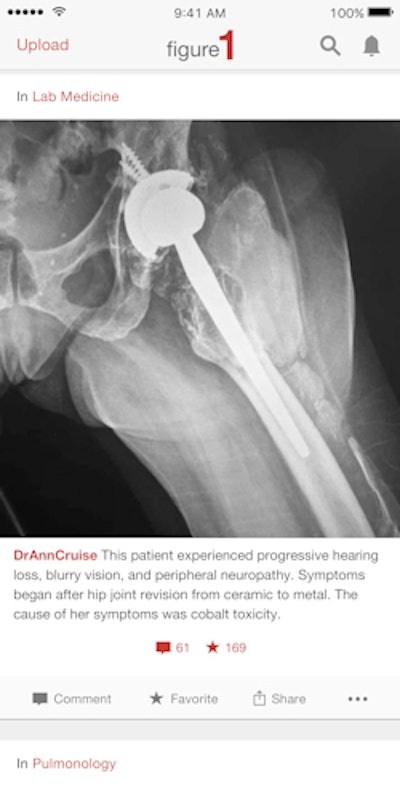

Figure 1 allows physicians to upload deidentified images and photos of cases and get feedback and opinions from other users. Because cases are constantly uploaded, users can learn on an ongoing basis.

Landy noted that radiologists were probably the only group of Figure 1 users who didn't want to use their phones to capture images, and that radiologists have helped the company develop a lot of the features that are now a regular part of Figure 1's service. For example, the recently relaunched Web version of Figure 1 was built for radiologists and other physicians who use desktop computers.

In addition, Landy said that one of his favorite features on Figure 1's mobile app -- one that only applies to radiologists -- allows users to scroll through a stack of images by sliding a finger up and down the screen.

"You can now upload a full stack of CT or MR images on to Figure 1, and scroll through them like you would with a mouse [on a PACS workstation], but using your finger on a screen," he said.